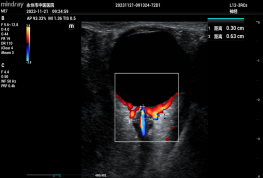

重症医学科医生为动脉瘤患者行TCCD检查

脑血流评估 ONSD测量